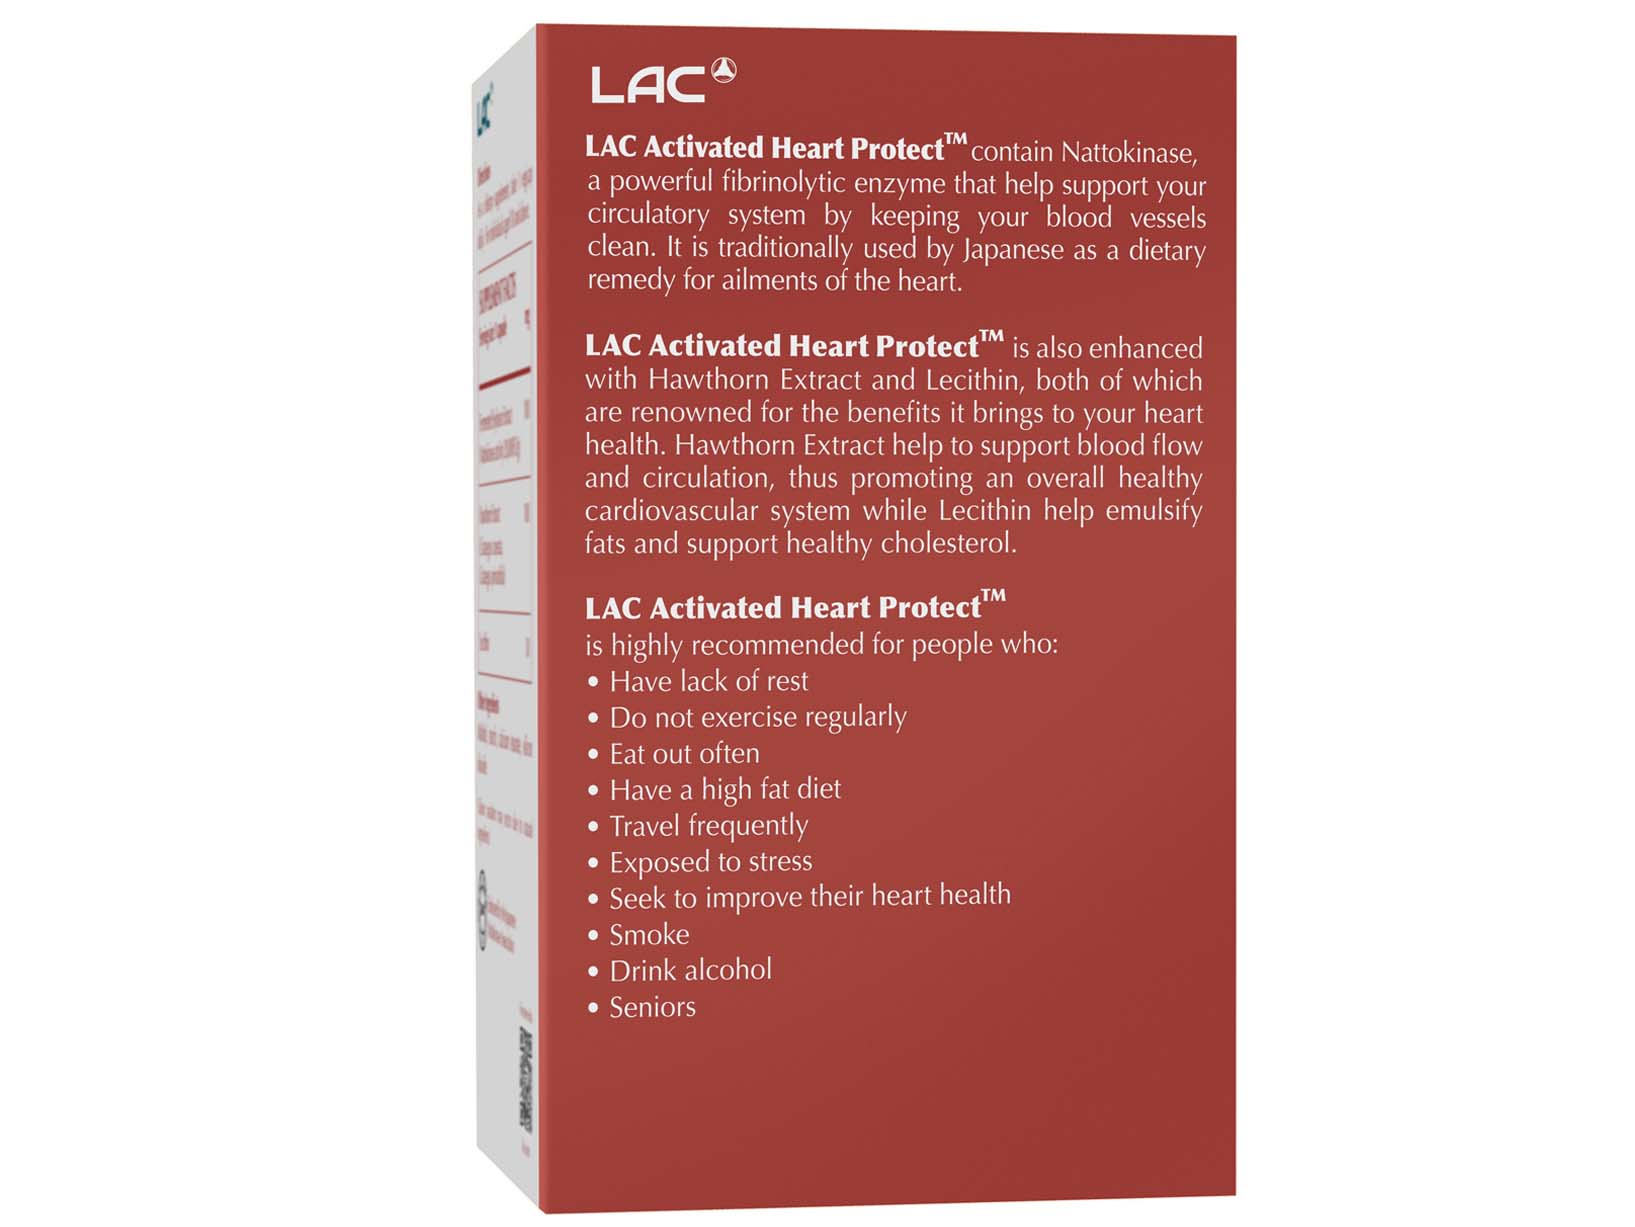

LAC ACTIVATED HEART PROTECT™

| Ingredients | Amount Per Serving |

| Fermented Soybean Extract

(Nattokinase Activity 20,000FU/g) |

100 mg |

| Hawthorn Extract (Crataegus cuneata, Crataegus pinnatifida) | 100 mg |

| Lecithin | 30 mg |

| Net Weight/pcs | 0.07 kg |

| Direction of Use | As a dietary supplement, take 1 vegicap daily. For individuals aged 18 and above. |

| Serving Size | 1 Vegicap |

| Servings per Container | 30 |

| Country of Origin | Manufactured in Japan |